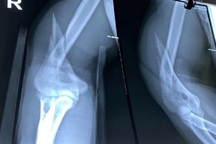

Sau khi chơi vật tay với bạn, nam thanh niên đau đớn dọc cánh tay phải, phải nhập viện điều trị (Ảnh: Bệnh viện cung cấp).

Do khi vật tay, chấn thương có nguy cơ xảy ra do lực xoắn tập trung vào đoạn giữa thân xương cánh tay, nơi có rãnh xoắn, làm tăng nguy cơ gãy xương kiểu xoắn. Đây cũng chính là khu vực mà thần kinh quay đi qua nên nếu tổn thương lan rộng, có thể gây yếu hoặc liệt vận động các cơ duỗi của cổ tay và ngón tay.